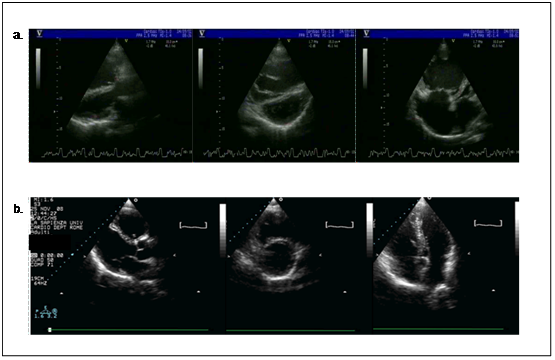

Patient 3 is a 48-year-old woman who received a diagnosis of iPAH in 1999. Since 1998 she had dyspnoea and progressive reduction of effort tolerance, and these symptoms worsened during the last 2months of pregnancy. Just few days after the delivery she had an echocardiographic evaluation that showed an estimated systolic PAP of 100mmHg, so she was referred to our center. At first evaluation, the patient presented jugular distension (1-2/4), hepatomegaly and mild peripheral oedema; she was NYHA/WHO functional class III and showed a decreased exercise capacity (6MWD 330m, (Figure 4)); ECG showed right ventricular strain; respiratory function tests, perfusion lung scan and autoanticorpal assessment were normal. The patient underwent RHC that confirmed the diagnosis of moderate-severe precapillary PH with positive response to acute vasoreactivity test with iNO 20ppm (mPAP from 46 to 36mmHg, CI from 2.8 to 3.6 l/min/m2, PVR from 7.8 to 4.7WU) (Figure 4). According to these results, the patient was started on a calcium channel blocker (nifedipine 90mg/die; it was not possible to increase the dose because of severe peripheral oedema). After 1year of treatment, the patient showed a substantial increase in effort tolerance (6MWT from 330 to 470m, (Figure 4) and improvement of NYHA/WHO functional class (from III to II), but in the following 3months exercise capacity worsened, so oral beraprost was added at the dosage of 40μgqid and increased at the maximum tolerated dose (400μg/die). During the first year, the patient had a transient improvement in clinical status and exercise capacity, but during the following months she had a new severe deterioration, returning to NYHA functional class III. We performed a hemodynamic evaluation that revealed a significant worsening of pulmonary hypertension (mPAP 90mmHg, CI 2.8l/min/m2, PVR 14.4WU). Moreover, there was no more vasoreactivity. At that time we discussed the opportunity to start epoprostenol, but the patient refused the implantation of the intravenous line. For this reason we decided to suspend beraprost and nifedipine, and start bosentan (62.5mg bid for the first 4week, followed by 125 mg bid). After four months she had minimal clinical improvement and a RHC showed a decrease in PAPm, and PVR but also CI was reduced (mPAP 65mmHg, CI 2.2 l/min/m2, PVR 13 WU) (Figure 4). So epoprostenol was started and up-titrated to the maximum tolerated dosage (up to 46ng/kg/min during a 10years follow-up). During this period we obtained a progressive and sustained improvement of clinical status (WHO class II) and effort tolerance (6MWD above 500m). At the ECG we observed a reduction in RV strain and echocardiography documented a reverse remodelling of RV geometry (Figure 5). RHCs performed 2 and 4years after starting epoprostenol revealed a progressive improvement of pulmonary hemodynamics (mPAP from 65mmHg after bosentan treatment to 51 and 36mmHg, respectively); last evaluation confirmed the results obtained (Figure 4). Flushing and jaw pain were the most frequent side effects referred by the patient during follow-up. Liver function tests have been monthly performed, remaining between normal values. The patient never presented CVC infection in her clinical history.

Figure 5PATIENT 3: Reverse remodelling of cardiac geometry during follow-up.